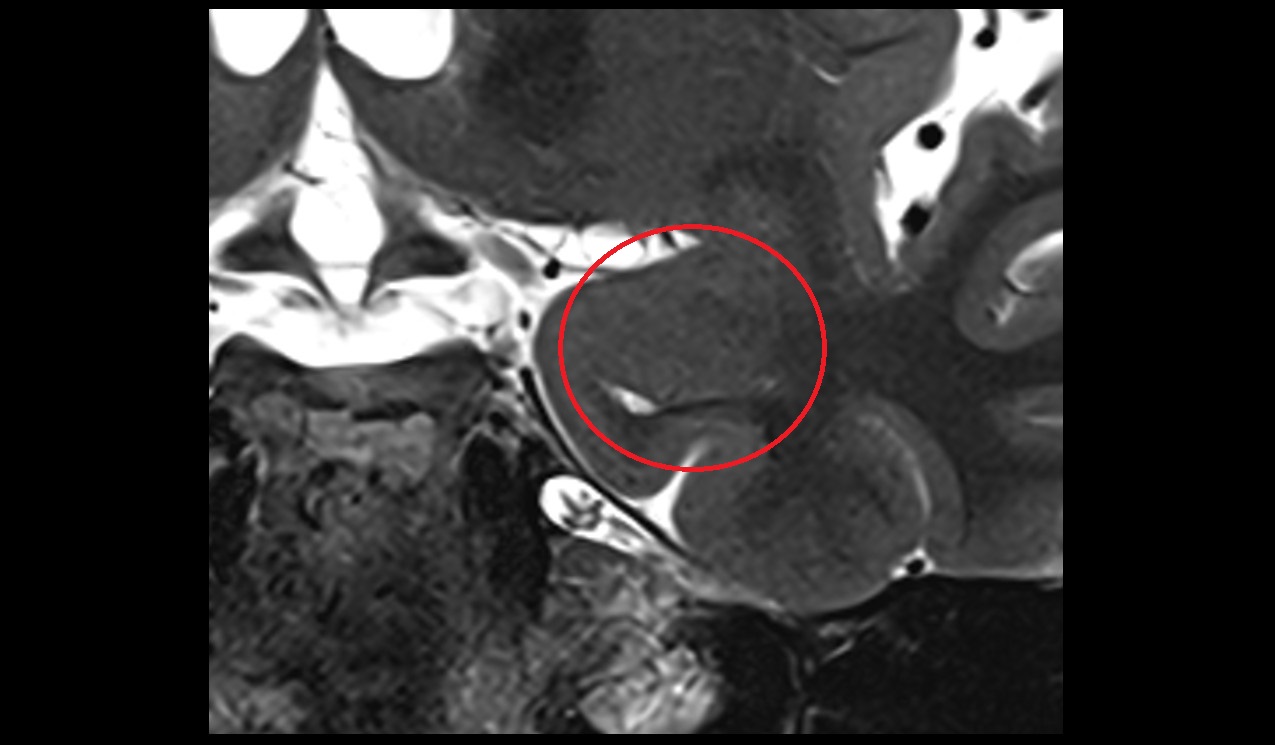

- Meckel’s cave (Trigeminal cave)

- Trigeminal cave